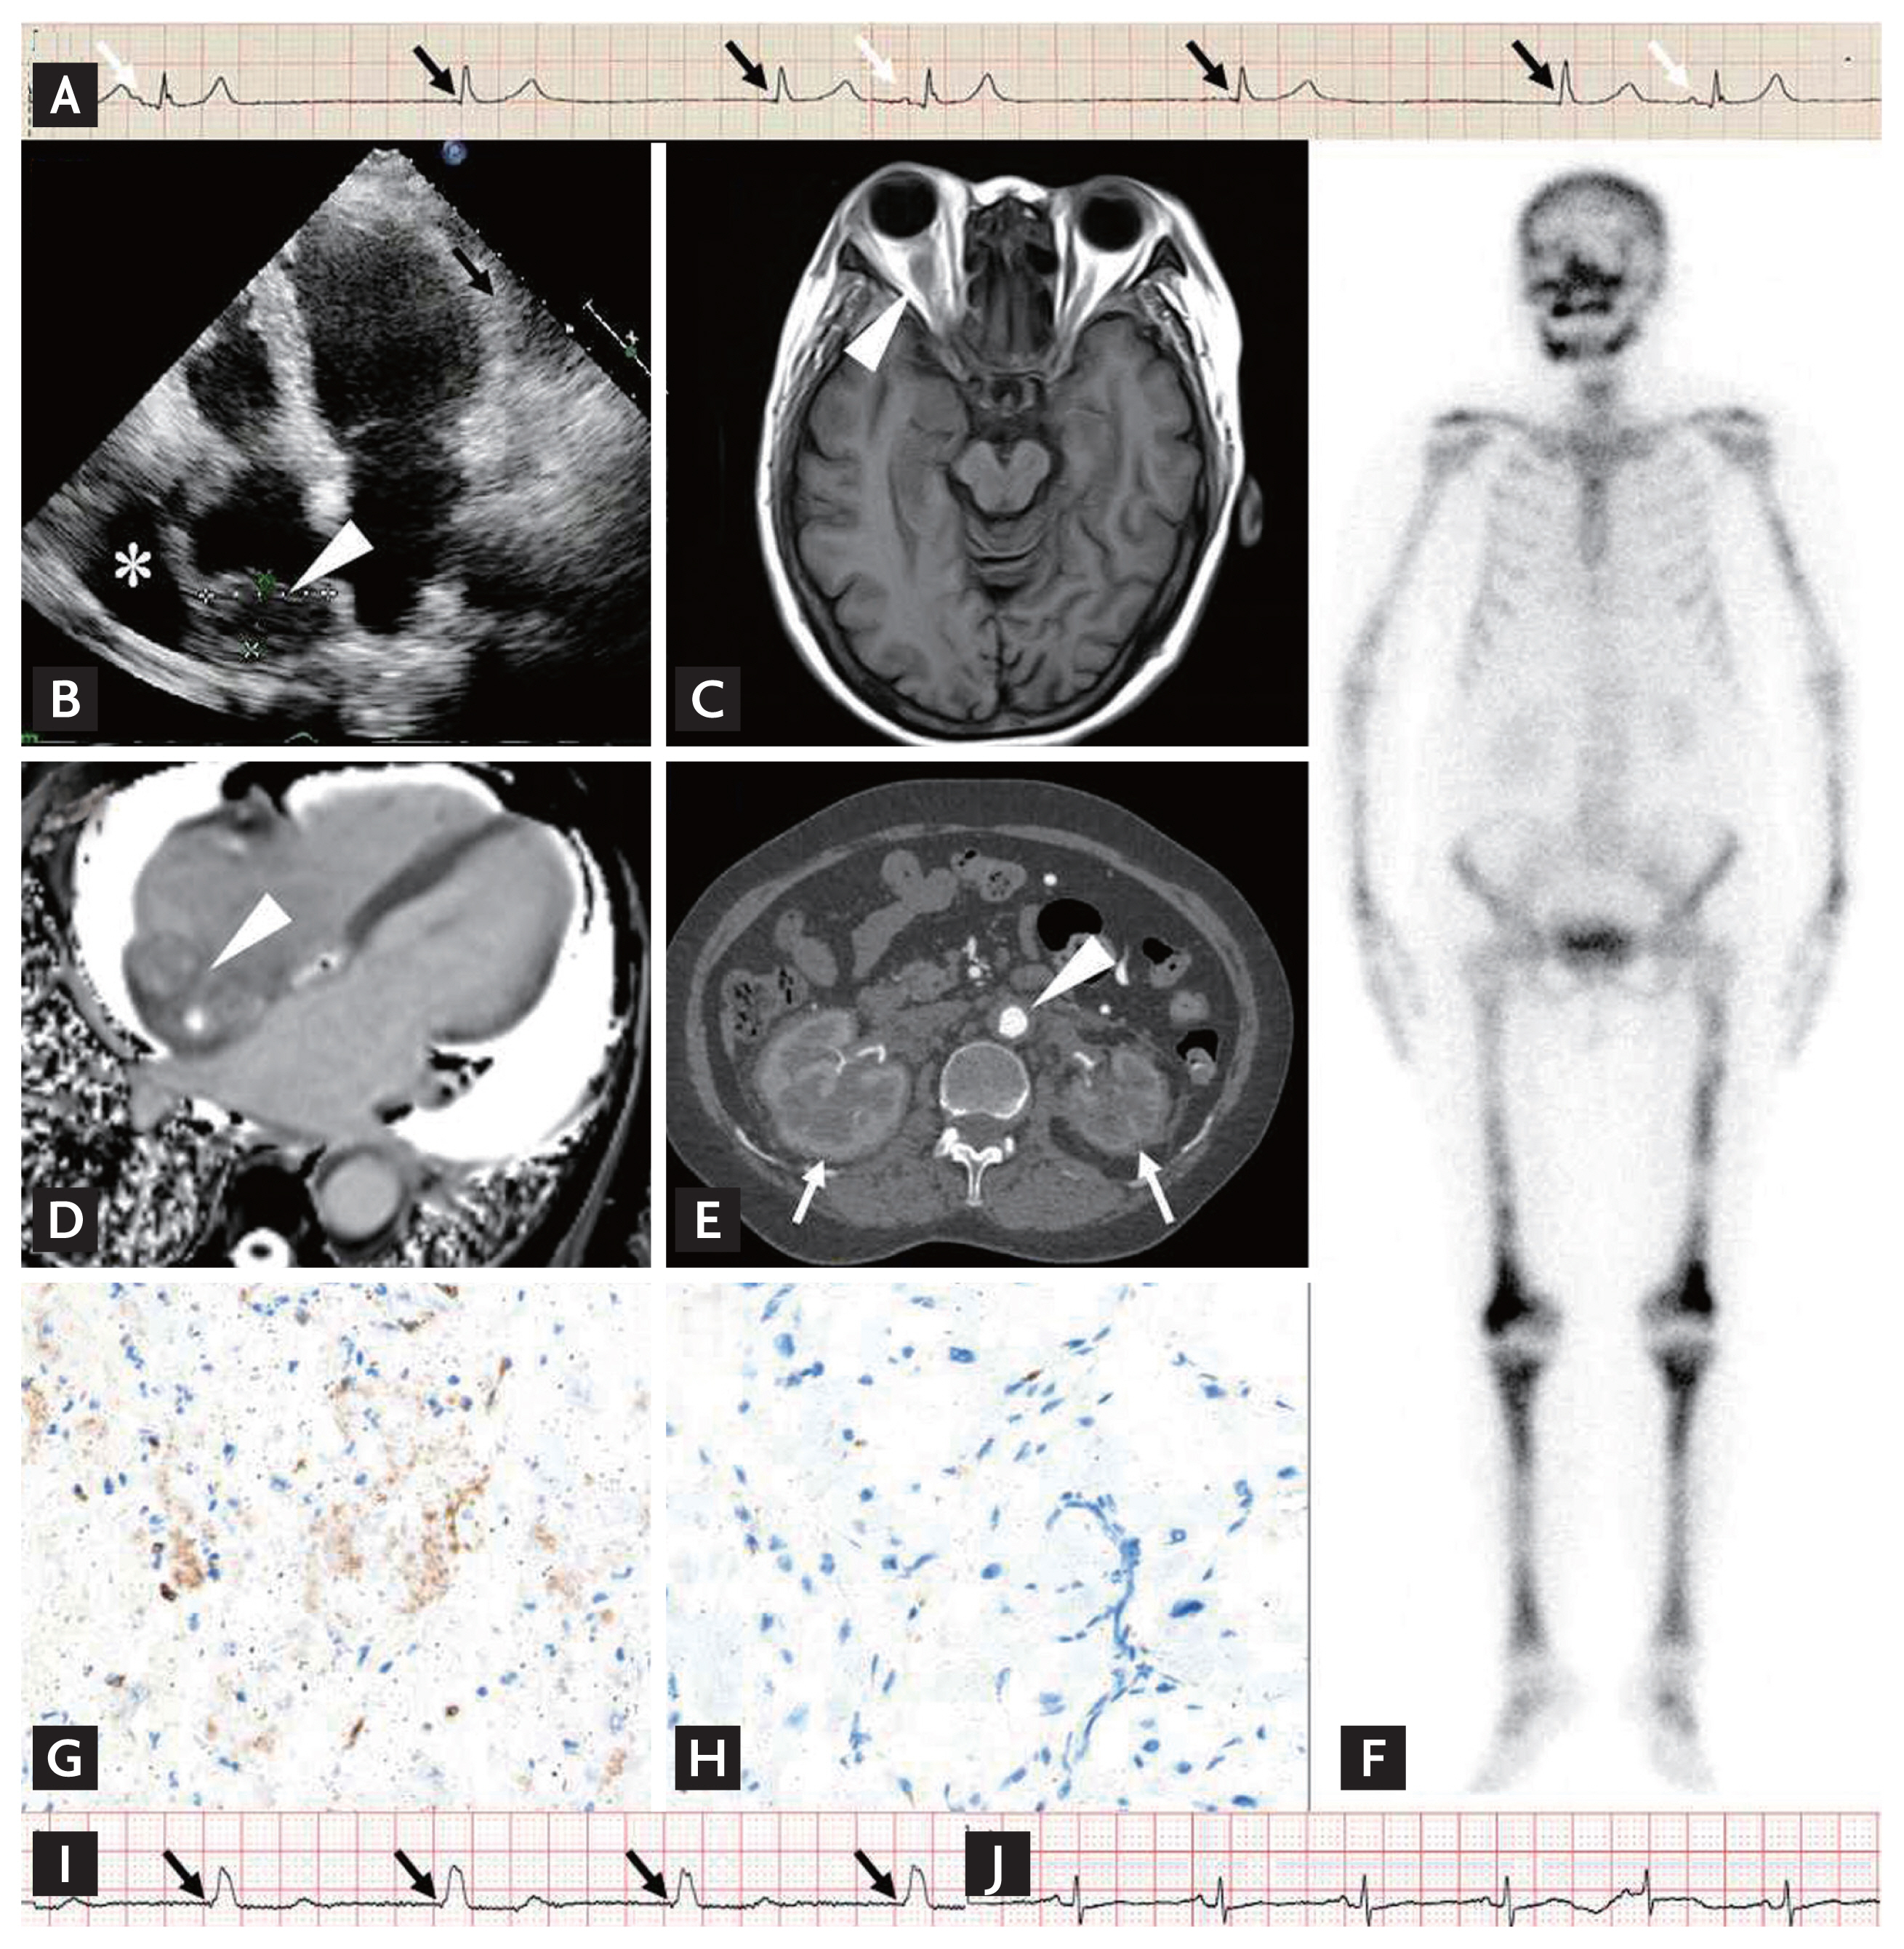

A 64-year-old woman was admitted because of progressive exertional dyspnea for 4 years and recurrent syncope for 2 days. A diagnosis of sinus node syndrome (SSS) was confirmed based on sinus arrest with atrioventricular junctional escape rhythm on electrocardiogram (Fig. 1A). Further cardiac and neurological examinations revealed a mass on right atrium (RA) and pericardial effusion on echocardiography (Fig. 1B), and a right retro-orbital lesion with normal T1-hypointense enhancement but short T2hypointense enhancement (Fig. 1C) on cerebral magnetic resonance imaging (MRI), indicating Erdheim-Chester disease (ECD). Ancillary imaging examinations further demonstrated typical features of ECD, including the irregular mass on the RA and a right atrio-ventricular groove with relatively shorter T1 and longer T2 relaxation times (Fig. 1D) on cardiac MRI, a ‘coated aorta’ and a ‘hairy kidney’ (Fig. 1E) on computed tomography, and symmetrical increased uptake of radiotracer in the skull and long bones of the extremities (Fig. 1F) on bone scintigraphy. ECD was finally confirmed by myocardial mass biopsy with typical histological and immunohistochemistry findings of CD68(+), CD1a(−), S100(−) (Fig. 1G and 1H) with negative BRAFV600E mutation. A single chamber ventricular pacemaker was implanted for SSS treatment, and 3 million units of interferonalpha was administered twice a week for ECD treatment. The patient was pacemaker-dependent at the 2-month follow-up (Fig. 1I), but displayed a restored intrinsic sinus rhythm after 4 months of interferon-alpha treatment (Fig. 1J).

As a non-Langerhans cells histiocytosis with multiorgan involvement, 70% of patients with ECD have abnormal heart imaging. The most common finding is RA infiltration. In a previous similar case with RA involvement and SSS, an RA lead was implanted in an area with a less thickened wall and no delayed enhancement on cardiac MRI. However, we abandoned the RA approach in consideration of not only the technical difficulties, but also the progression of infiltration that might compromise pacing function. Moreover, the patient experienced SSS remission after interferonalpha treatment, but longer follow-up was needed to observe the long-term effect.